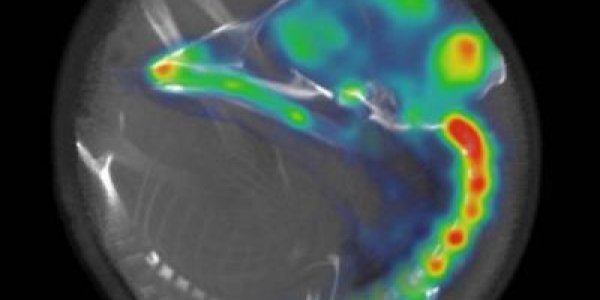

Badly controlled diabetes are known to affect the brain, causing memory and learning problems and even increased incidence of dementia. How this occurs is not clear but a study in mice with type 2…